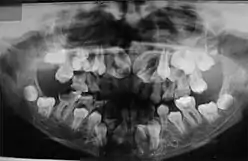

O diagnóstico do portador de DCC é realizado através de exames clínicos e radiográficos. A aparência clínica dos acometidos é bastante característica, principalmente após a puberdade devido a alguns traços dessa doença, como baixa estatura, falha na erupção dos dentes permanentes, dentes supranumerários e retardo na esfoliação dos dentes decíduos. Outros aspectos dessa patologia são: a aplasia ou hipoplasia clavicular (clavículas rudimentares ou completamente ausentes), que está presente em 10% dos casos, que permite o movimento do braço até ao plano sagital mediano. A abóboda craniana aumentada, uma menor espessura do músculo masseter, hipodesenvolvimento do terço médio da face, geralmente também é apresentado uma hipoplasia da maxila, retardo no desenvolvimento esquelético, o pescoço largo e atraso no fechamento das suturas cranianas. Em alguns casos é possível observar que os palatos estreitos e profundos também são frequentes. É importante realizar o diagnóstico diferencial devido aos pacientes exibirem nanismo, ossos densos, frágeis e agenesias parciais das falanges dos dedos dos pés e mãos.[9][10]

No estudo realizado por McNamara et al. (1999) sobre as características da síndrome, encontradas nas radiografias panorâmicas, citam-se a presença de múltiplos dentes não irrompidos; dentes com alterações de forma; ramos ascendentes da mandíbula delgados com os bordos posterior e anterior paralelos e, em alguns casos, estreitando-se em direção ao processo coronóide e côndilo; processo coronóide frequentemente ascendente e para posterior; arco zigomático estreito com severa inclinação descendente e algumas vezes descontínuo com a sutura zigomático-temporal; seios maxilares pequenos ou ausentes; bordo infraorbital mais baixo que o normal em relação aos dentes; inclinação descendente do assoalho da fossa nasal em relação à espinha nasal anterior, acentuando a forma em V; trabeculado ósseo da mandíbula com aspecto grosseiro; aumento da densidade da crista óssea alveolar, comprometendo a irrupção dentária; aumento da densidade do ramo ascendente entre o bordo anterior da mandíbula e o canal dentário inferior. A maior parte dos pacientes com disostose cleidocraniana desempenha suas funções normais, não apresentando comprometimento significativo. Existem relatos de que o tratamento cirúrgico com a exposição dos dentes inclusos, combinado com o tratamento ortodôntico, tem sido bem-sucedido em alguns casos (McDONALD, 2001). Porém, a extração dos dentes decíduos não promove a erupção dos dentes permanentes inclusos.[11]

Sabe-se que a retenção prolongada dos dentes decíduos, agenesias e dentes supranumerários provocam má oclusão. Portanto, procedimentos ortodônticos devem ser utilizados com a finalidade de adequar a cavidade bucal para futura reabilitação protética. Os exames radiográficos, além de auxiliar na detecção das anormalidades maxilofaciais, permitem o acompanhamento dos pacientes, sendo, por isso, considerados uma ferramenta para o diagnóstico e conduta terapêutica.[11]

As anomalias orais causadas pela disostose cleidocrania são marcantes, e geralmente, são fatores determinantes para o diagnóstico da DCC, tornando o cirurgião-dentista parte crucial para a descoberta da doença.[12] Estas anormalidades apresentadas pelos pacientes que possuem disostose são numerosas e estão presentes principalmente na dentição decídua, mas também podem aparecer na permanente. São elas: Anodontia parcial (ausência do elemento dentário), dentes supranumerários, erupções tardias, dentição ectópica (fora do local adequado) e anomalias dentárias, palato alto, estreito e arqueado, assim como, subdesenvolvimento da maxila e seios paranasais, alteração de densidade óssea e aumento da espessura da fibromucosa (gengiva)[13],[8],[14],.[12]